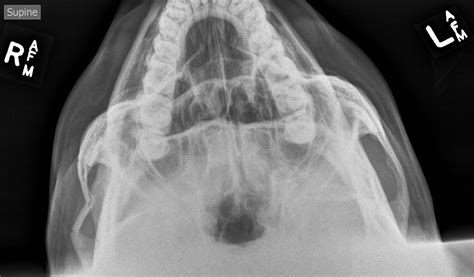

Diagnosing a fracture of zygomatic complex requires a combination of a thorough physical examination and advanced imaging. Physicians typically begin with a clinical assessment, checking for symmetry, sensory changes, and visual alignment. Following this, imaging is non-negotiable for precise diagnosis.

Computed Tomography (CT) scans, specifically axial and coronal views, remain the gold standard for diagnosing these fractures. CT imaging allows the surgeon to visualize the exact degree of displacement, the involvement of the orbital floor, and any potential herniation of orbital contents into the maxillary sinus.